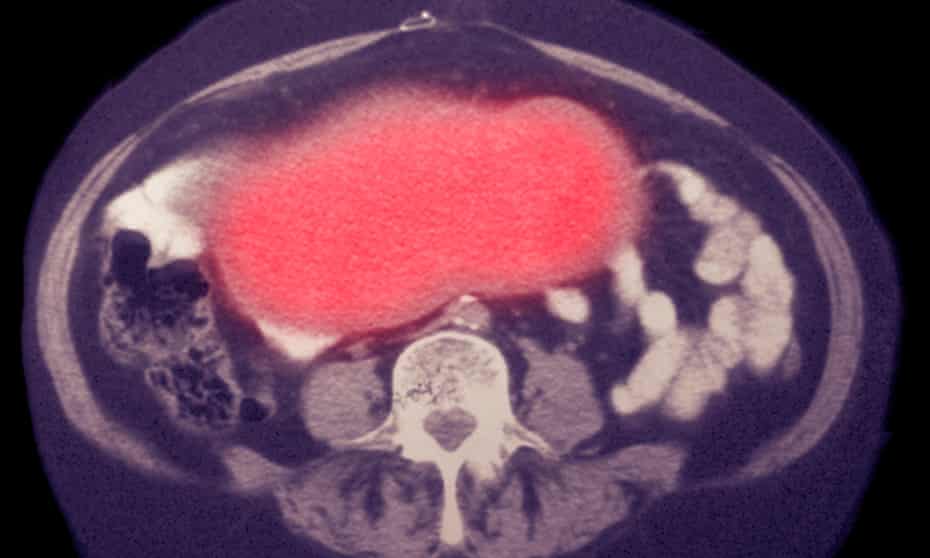

El cáncer de ovario es responsable de la mayor proporción de muertes asociadas con cánceres ginecológicos. Actualmente, el 75% de los cánceres de ovario se diagnostican en una etapa tardía, cuando los tumores se han diseminado. Ser capaz de detectar la enfermedad antes puede mejorar los resultados del tratamiento.